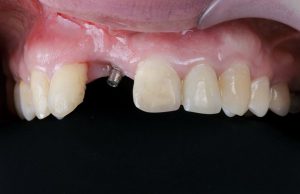

تحلیل لثه

اگر بافت لثه اطراف ایمپلنت شروع به تحلیل رفتن کند، می تواند پایه فلزی ایمپلنت را نمایان کند. این اغلب در نتیجه عفونت یا قرارگیری نامناسب ایمپلنت ها رخ می دهد.

| رنگ و حجم لثه | قرمز روشن. حاشیه لثه به وضوح مشخص در اطراف گردن ایمپلنت. | قرمز، آبی، سفید. لثه ها عقب می روند. گردن ایمپلنت و استخوان نمایان می شوند. |